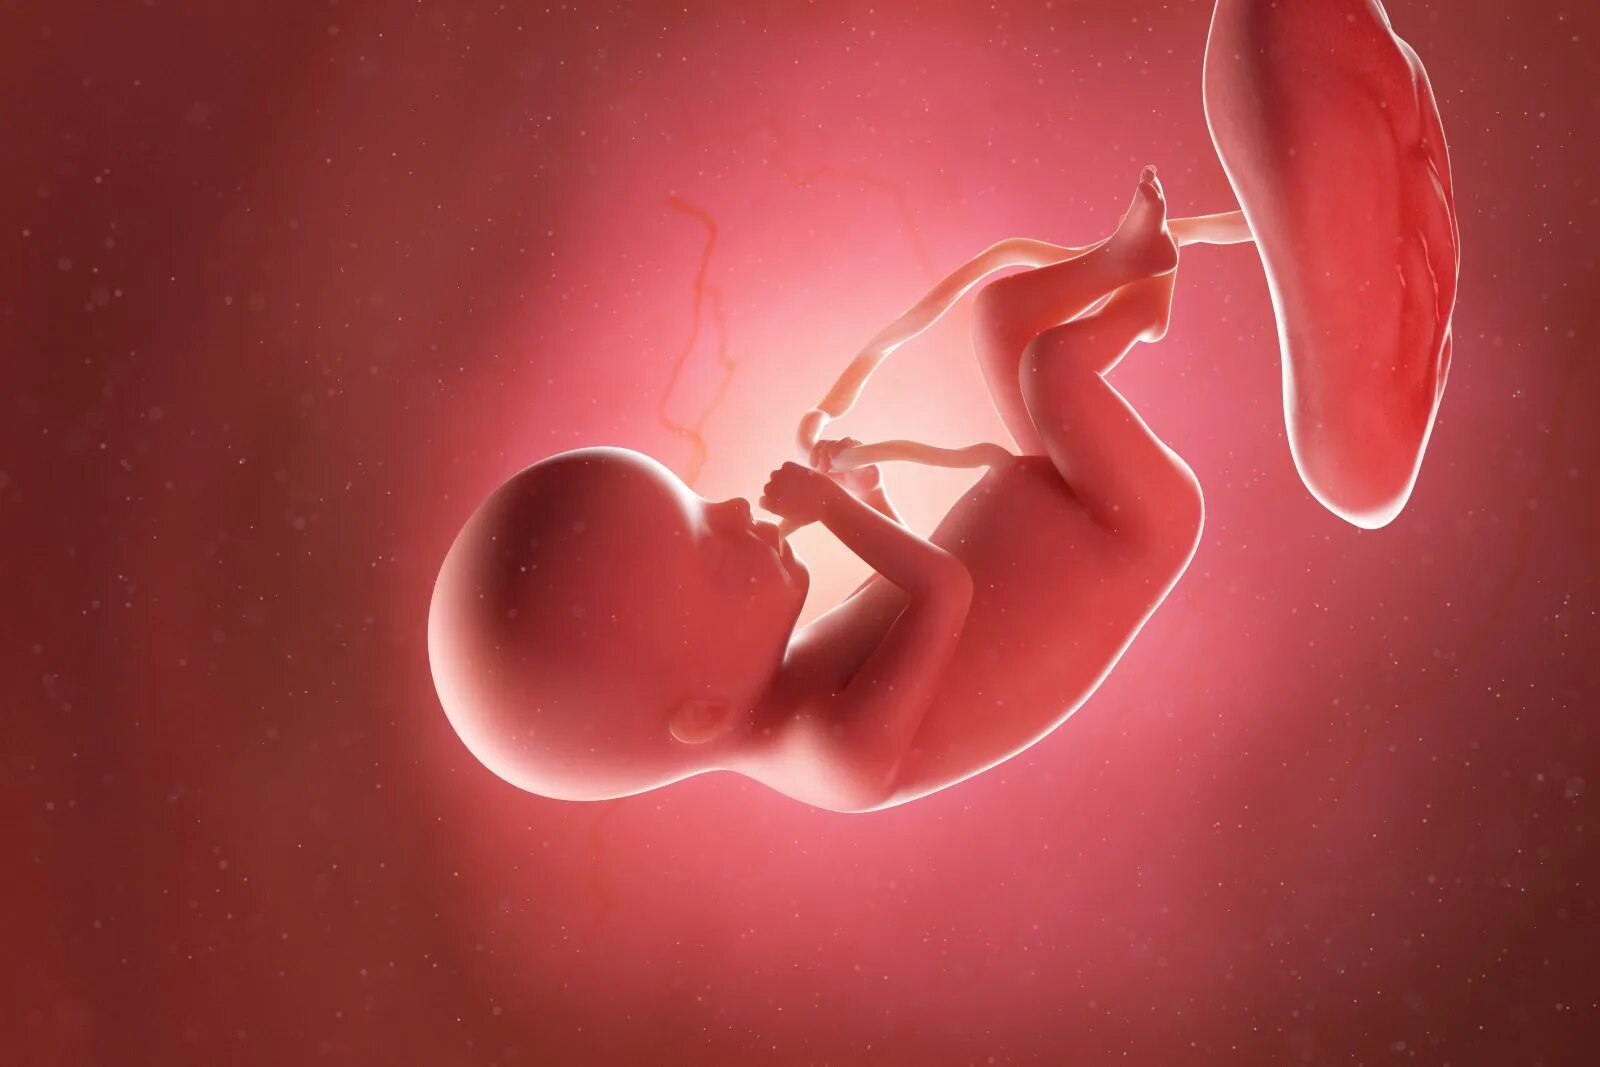

20 недель часто шевелится